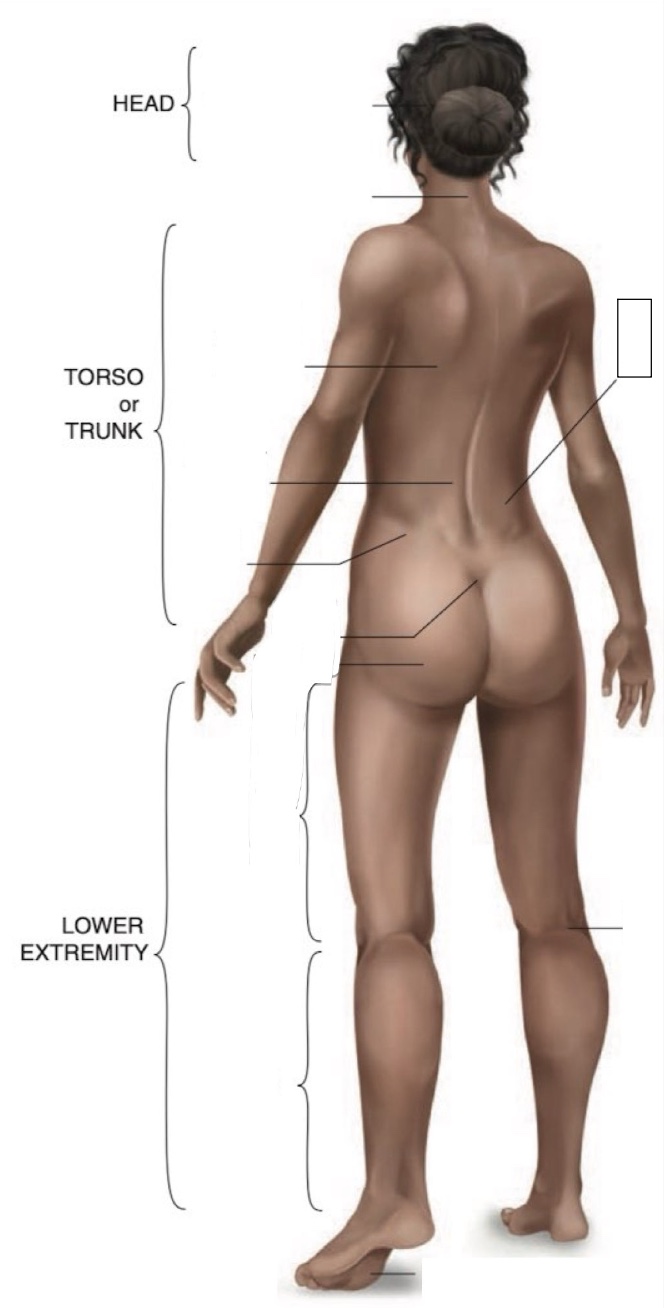

Occipital region

Cervical region

Inferior angle of scapula

Lumbar region

Iliac crest

Sacral region

Buttock

Thigh

Leg

Flank

Popliteal region